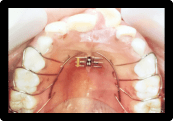

症例3:叢生の矯正治療

BEFORE

AFTER

症例概要

年代・性別

10歳代 女性

主訴

歯並びを良くしたい

治療内容

ブラケット(ワイヤー)を用いた矯正治療

治療期間

4ヶ月

治療のリスク

定期検診、セルフケアを怠ると虫歯になる可能性があります

治療費用

440,000円(税込)